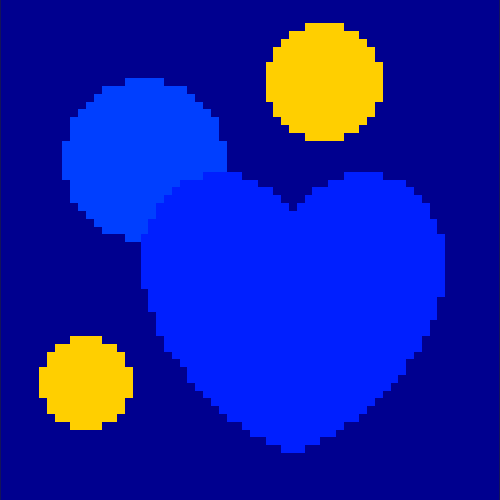

The first data set consists of a heart-shaped region and three circles on a static background (see figure 1 (a)). The two smaller circles are assumed to belong to

the same tissue type and therefore to the same subregion, which causes a total of four subregions, including the background. To simulate a more realistic application of dynamic SPECT

imaging, we used a synthesized representation of a rat liver as a second data set (see figure 1 (b)). The temporal concentration curves used to simulate the data sets

are shown in figure 2. As before, the total number of subregions was chosen to be equal to four in order to provide a both simple and realistic shape model.